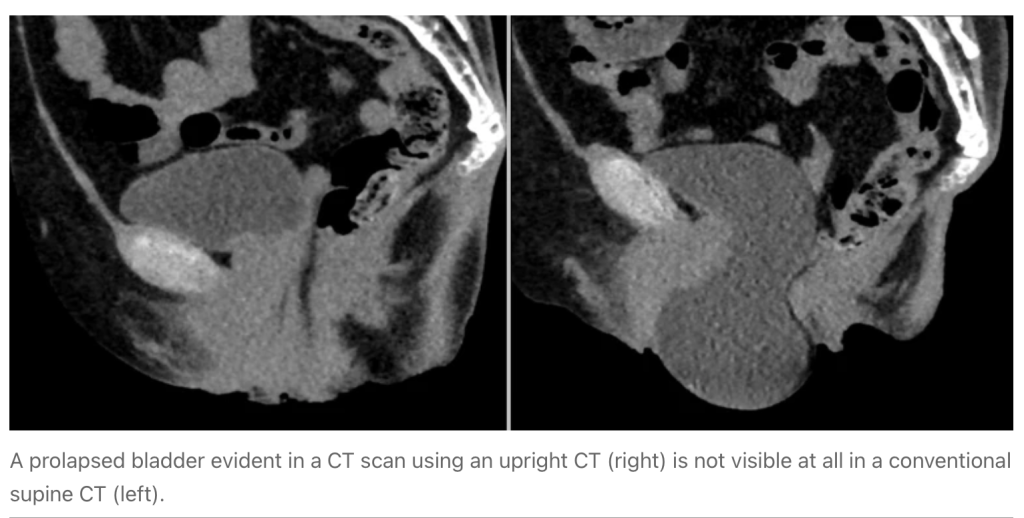

L’esecuzione di un esame TC in posizione eretta (upright CT) porterebbe alla visualizzazione di nuove informazioni anatomiche in termini funzionali, come la riduzione in volume delle principali vene vicino al torace, disturbi della deglutizione, della postura e della minzione.